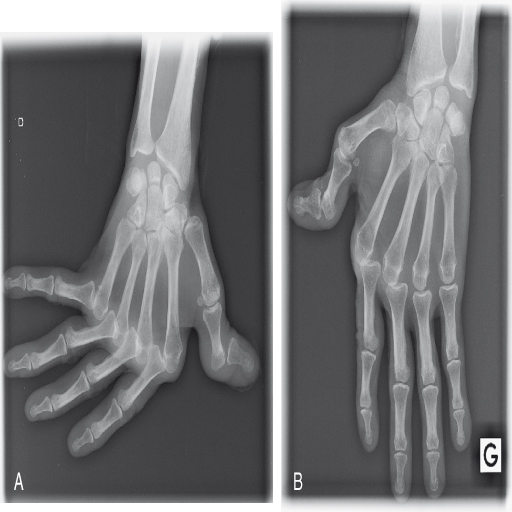

intéressant principalement les genoux, le carpe, et les articulations des doigts, notamment les articulations interphalangiennes proximales. Les atteintes proximales et axiales sont plus inhabituelles. L'analyse du liquide articulaire est difficile. En effet, les épanchements sont rares et de toute façon peu abondants. Le liquide est faiblement inflammatoire. Exceptionnellement, on observe des déformations liées à une subluxation des tendons des doigts dénommée rhumatisme de Jaccoud (fig. 16.1). Une des particularités sémiologiques de cette atteinte est la réductibilité des déformations. Des ténosynovites (surtout des fléchisseurs des doigts) sont possibles. Les monoarthrites sont rares et doivent faire évoquer une complication infectieuse

Fig. 16-1 : A. et B. Lupus érythémateux disséminé. Arthropathie lupique avec main de Jaccoud.